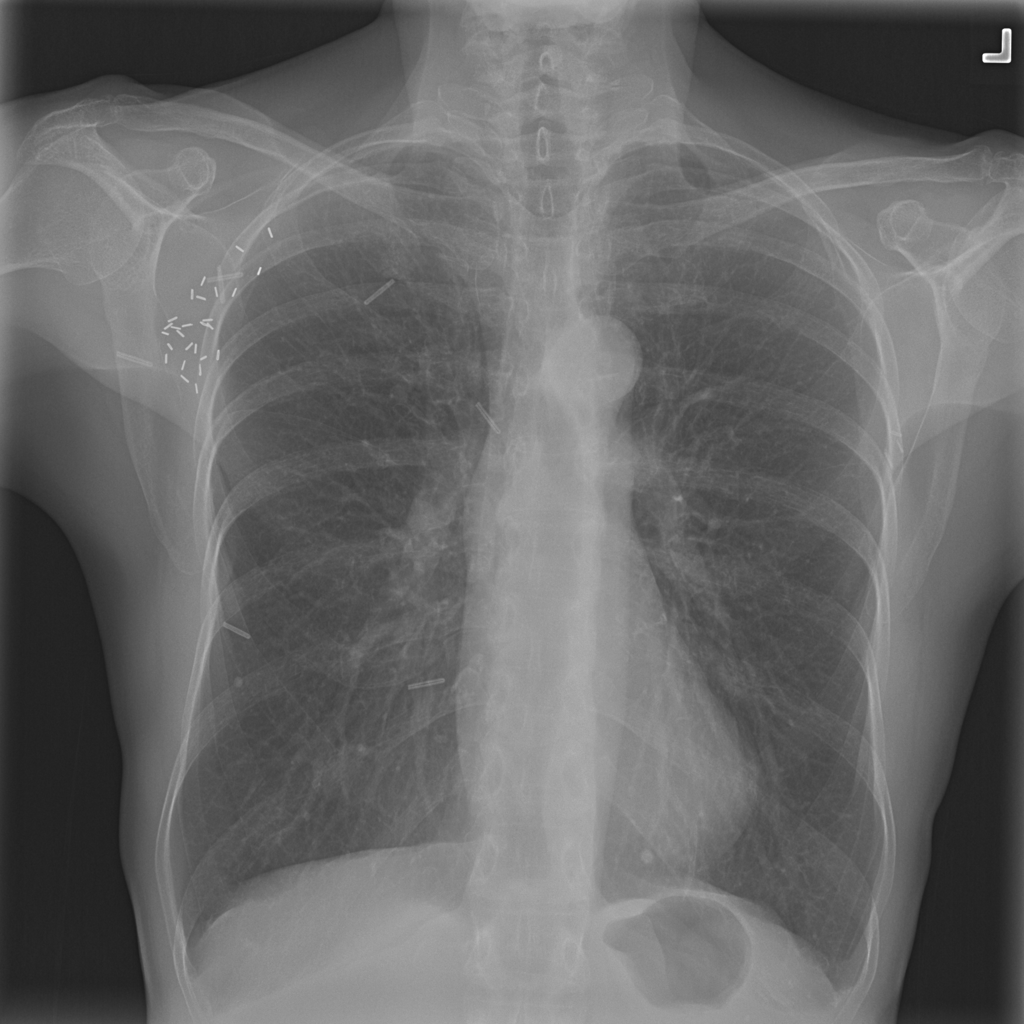

Nodule representative X-ray

Reference image: PAT-894B · IMG-002 · Bounding-box highlight from source annotation where available.